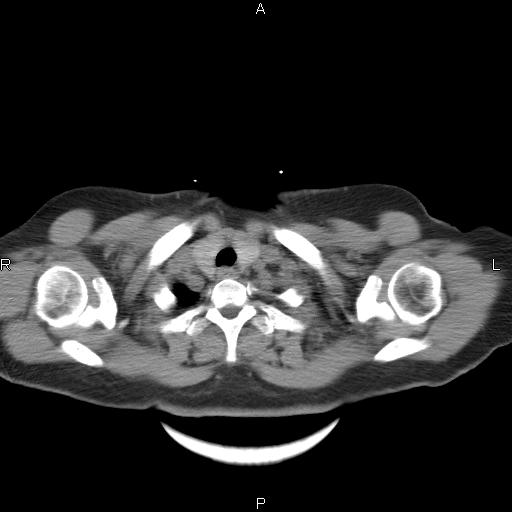

女、63Y 双眼睑下垂,早轻晚重。 胸腺瘤???

结果胸腺瘤